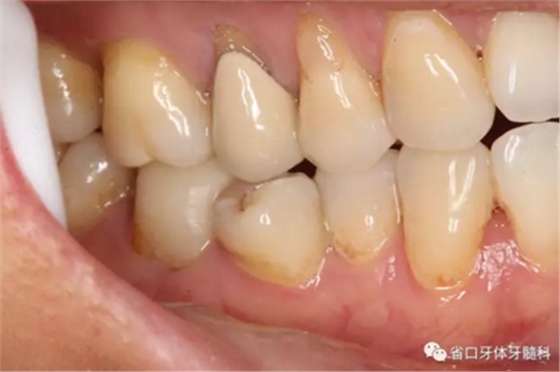

圖4 牙體預備后頰側觀

圖9-11 嵌體試戴粘接后,窩溝形態(tài)和、染色有待改進

圖12-14 術后1年回訪:無明顯食物嵌塞,咬合關系良好,牙周健康,未見瘺管

圖15-17 術后1年5個月回訪:患者使用良好,無明顯食物嵌塞,牙周健康,瘺管未見復發(fā)。